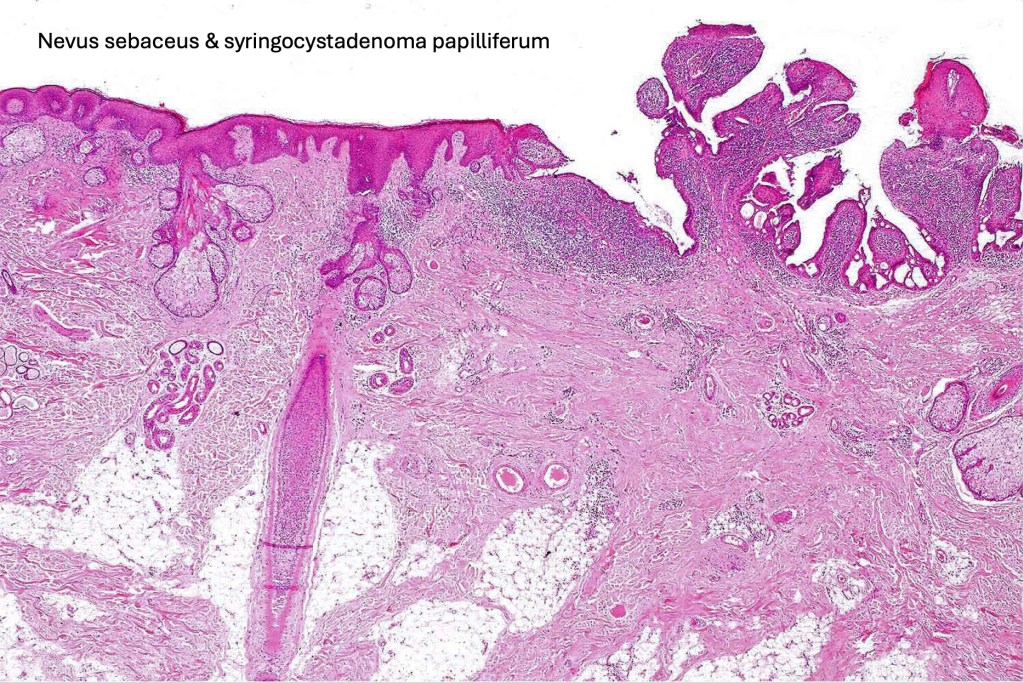

•A common tumor in a background of nevus sebaceus

•Scanning magnification shows an exophytic tumor or an epidermal invagination enclosing epithelial covered papillae with a fibrovascular core

•Glands are present at the base of the lesion

•At the edges, the squamous epithelium is in continuity with the glandular one

•The epithelium consists of outer myoepithelial cells supporting an inner layer of columnar cells with abundant eosinophilic cytoplasm showing decapitation secretion

•Dense plasma cell infiltrate